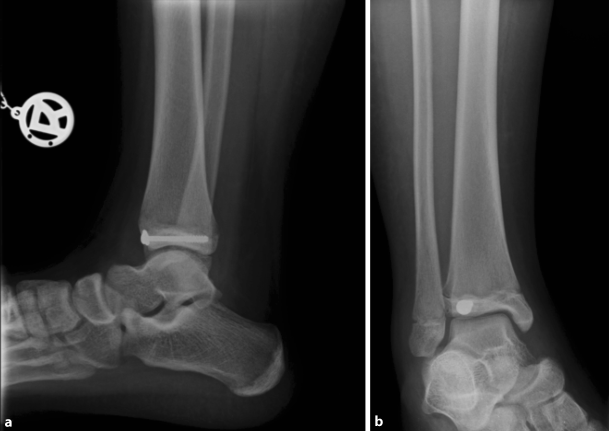

An exemplary case of a 14-year-old patient with a surgically treated Tillaux fracture is presented in Figs. 2 to 5 (Fig. 2a, b, X‑ray; Fig. 3a, b, CT scan; Fig. 4a, b, X‑ray after open reduction and screw fixation; Fig. 5a, b, X‑ray in two planes after screw removal).

Fig. 2

Initial X‑ray in two planes of a Tillaux fracture in a 14-year-old patient (a anteroposterior view, b lateral view)

Bild vergrößern